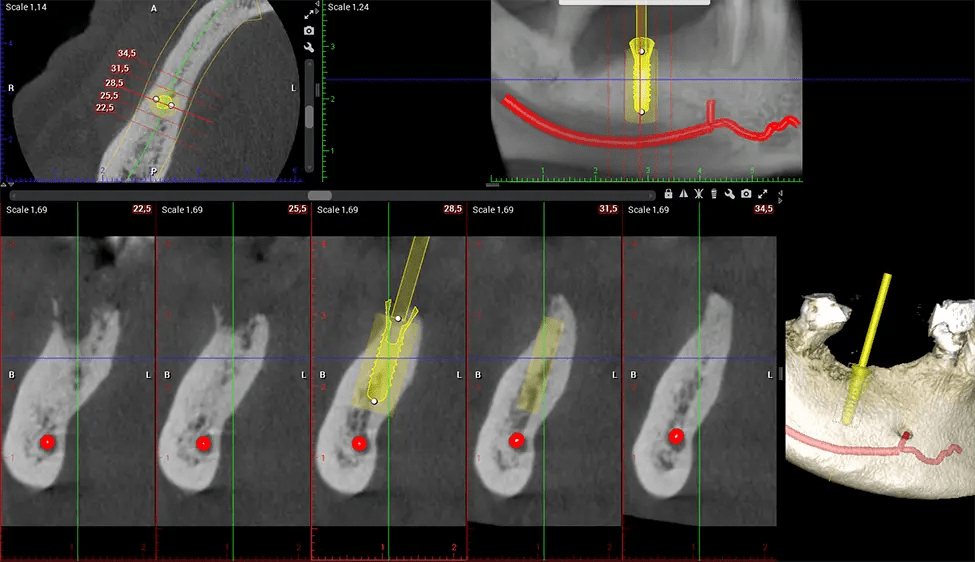

Cone Beam Computed Tomography (CBCT) is an advanced imaging technique used in dentistry and maxillofacial surgery to obtain detailed 3D images of the oral and maxillofacial structures. At Dr G Dental Studio, our CBCT scanners utilize a cone-shaped X-ray beam and a specialized detector to capture images from different angles. A computer then combines these images to create a 3D representation of the patient’s oral anatomy.

When paired with extractions, dental implant placement, or bone grafting, CBCT technology can provide you with a quicker and much more comfortable experience. This is because the 3D image provides a more detailed picture of your entire oral cavity, allowing your dentist to walk you through each step of the process before it occurs. This often helps patients feel more prepared and comfortable overall, especially if they have had a traumatic experience with past dental treatments.

After the scanning process, the captured X-ray images are processed by the CBCT software, which applies algorithms to reconstruct a detailed 3D image of the scanned area. The software compiles these individual X-ray images and creates a digital 3D representation of the patient’s anatomy. The reconstructed 3D CBCT image can be viewed and analyzed by the dentist or radiologist. This image can be manipulated, rotated, and zoomed in or out to examine specific structures and evaluate the patient’s condition.

Oral and Maxillofacial Surgeon Complex oral surgeries, orthognathic (jaw) surgery, and removal of impacted teeth. Offers precise, three-dimensional visualization of the skull, jaw, and craniocervical junction to enhance diagnostic accuracy and minimize surgical risks.